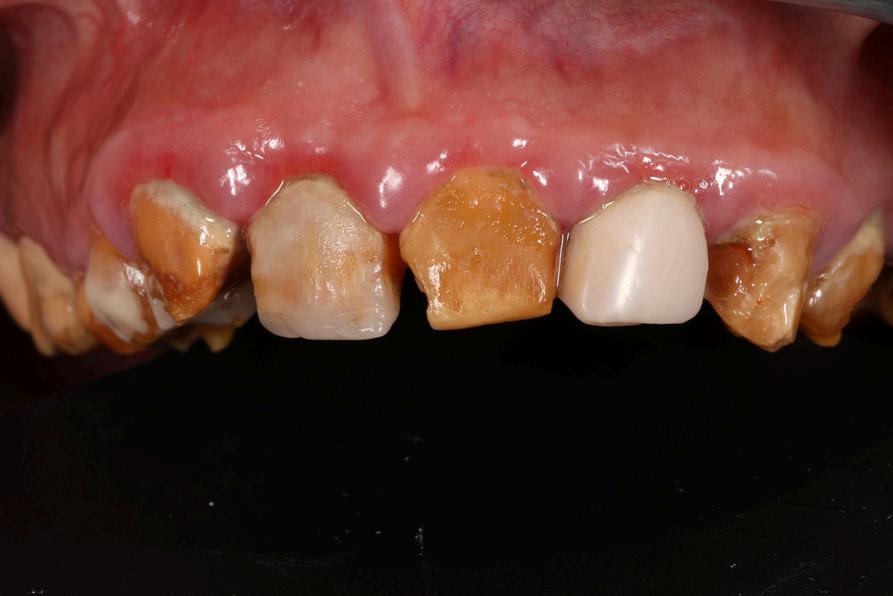

Se puede presentar Amelogénesis imperfecta, Hipomineralización molar incisivo, Hipoplasia del esmalte y por supuesto Caries dental

Se considera que los pacientes con

Celíaca tienen mayor riesgo de desarrollar defectos del esmalte (50%)

Es un defecto del tejido adamantino del diente, que durante su formación (amelogénesis), sufrió una alteración por causas genéticas, hereditarias, nutricionales o metabólicas

Este tejido puede estar tan dañado como que esté ausente total o parcialmente en el diente y generalmente afecta a todos los dientes primarios y permanentes.

Se encuentran varios tipos de Amelogénesis imperfecta: hipoplásica, hipomineralizada, hipomadura, hipomadura hipoplásica con taurodontismo, y 14 subtipos mas.

Esta patología cursa con pobre función y estética, hipo desarrollo maxilar, hipersensibilidad dentinaria, mala higiene, alto índice de caries asociada a otras condiciones generales (renales, respiratorias, alérgicas, genéticas), retardo en la erupción, baja autoestima y autoimagen, desinserción social y escolar. Se llega a definir como un problema familiar por lo complejo de los tratamientos y el largo período que se requiere para lograr el éxito.